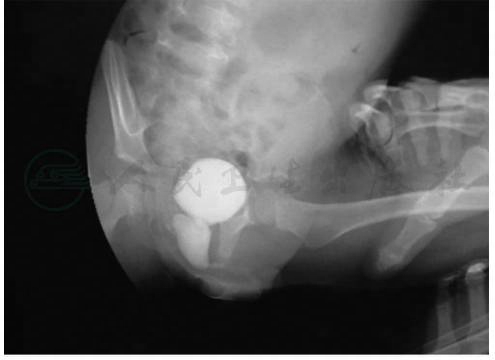

前列腺囊常伴发于重度尿道下裂,可以把前列腺囊分为5度:Ⅰ度 前列腺囊的深度仅数毫米;Ⅱ度 前列腺囊底部达膀胱颈;Ⅲ度 前列腺囊底部超过膀胱颈;Ⅳ度 前列腺囊底部超过精囊;Ⅴ度前列腺囊伴发其他米勒管残留组织。一般认为在会阴型及阴茎阴囊型尿道下裂中的发生率可达10%~15%。而Devine(1980)等报道会阴型尿道下裂中的前列腺囊发生率可达57%;亚洲报道最早的是Ikoma等(1986),在280例尿道下裂中27.5%合并前列腺囊。前列腺囊也可发生在无尿道下裂人群中。

前列腺囊可能是副中肾管退化不全,或尿生殖窦男性化不全的遗迹,开口于前列腺部尿道的后方。正常人的后尿道精阜中央有一小凹陷被称为前列腺囊。尿道下裂合并的前列腺囊拉长、向膀胱后方延伸,形成一个大的囊腔,可能并发感染及结石,也可影响插导尿管。如果并发感染,以反复附睾炎最常见。手术前往往感染症状少,但是在尿道成形术后由于尿道延长,增加了尿道阻力,易伴发附睾炎。可以通过排尿性膀胱尿道造影检出,尿道镜检查、超声及CT可明确其位置(图6,图7)。

图6前列腺囊

图7前列腺囊